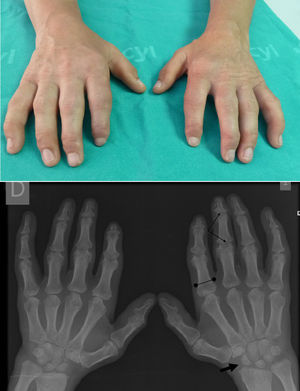

Manos en garra: imposibilidad para la flexión y la extensión máxima, sin que se objetive engrosamiento cutáneo ni afectación articular. Radiografía manos: huesos del carpo pequeños e irregulares (flecha) y falanges proximales anchas (línea acotada). La actitud en garra de los dedos produce una imagen de seudopinzamiento articular en IFP e IFD (flechas finas).

La ML III se manifiesta aproximadamente entre los 3 y 5 años de edad, con anomalías esqueléticas, alteraciones faciales, talla baja, inteligencia normal o retraso mental leve, opacidad corneal y escoliosis, a diferencia de otras formas de ML que sí tienen afectación visceral y un pronóstico vital sombrío en la infancia2,3. En la ML III la evolución es lenta, pudiendo alcanzar hasta la quinta década de la vida4. Las alteraciones óseas en la infancia pueden confundirse con artritis idiopática juvenil o esclerodermia, fundamentalmente por la afectación de las manos5,6. Los hallazgos radiológicos característicos de las manos son huesos del carpo pequeños e irregulares y falanges proximales relativamente anchas5 (fig. 1). En la columna lumbar, displasia vertebral con delineación irregular de los cuerpos vertebrales3, imágenes que se confirman en la RM (fig. 2). En la pelvis, displasia progresiva de las caderas, con acetábulos aplanados y destrucción de las cabezas femorales con coxartrosis secundaria2 (fig. 3).